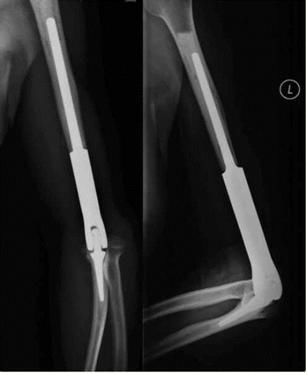

术后影像

“该手术是我院首次采用3D打印技术个性化定制假体,应用于骨肿瘤病人的治疗及重建,也是山东省首例。我们根据术前3D打印出来的截骨导板,将肱骨远端外侧病灶完整地精准切除,假体与切除后的骨质非常贴合;由于我们预先给假体做了多孔骨长入处理,将来假体可与正常骨质长在一起,这样假体的稳固性会非常好;术中我们重建了肘关节的功能性肌肉,所以,患者术后的屈伸及旋转功能很快得到恢复,这大大提高了患者术后的生活质量。”烟台山医院副院长常黎明介绍说,由上海交通大学医学院附属第九人民医院戴尅戎院士带领的上海交通大学医学3D打印创新研究中心成立于2016年,它是全国3D打印技术应用于临床医学的研究基地,获得国家“十三五”科技重大专项奖。而烟台山医院是烟台市骨科医学中心,其骨科是山东省临床重点专科。“我们医院在‘医工结合’的大形势下,目前已经与上海交通大学医学3D打印创新研究中心签署战略合作协议,我们也将马上成立上海交通大学医学3D打印创新研究中心烟台山医院分中心,这将进一步提升医院骨科的技术水平,切实满足更多患者的需求,让骨科疾病治疗更加个性化、精准化。”